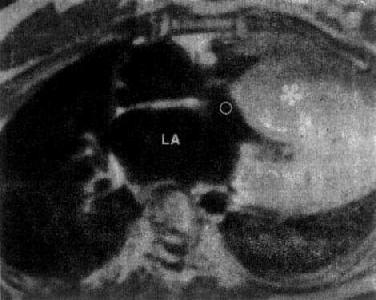

图3-2-28 特发性心肌病

心MRI,SE序列横断面图像,左心室壁及室间隔肥厚(*),LA左心房